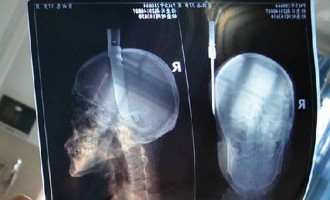

Ένα… “ιπτάμενο” μαχαίρι καρφώθηκε στο κεφάλι 57χρονου (φωτογραφίες)

Ένα απίστευτο περιστατικό συνέβη στην παλιά πόλη της Guangyuan στην Κίνα όταν άνδρας την ώρα που προχωρούσε αισθάνθηκε πόνο και…